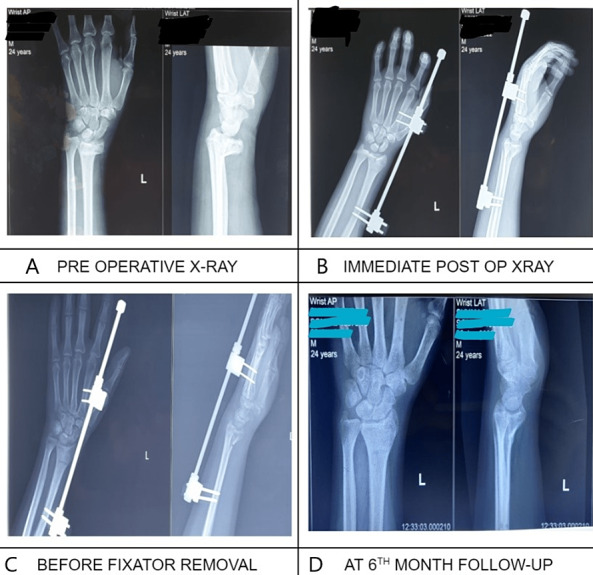

Fracture distal end radius is one of the most common fracture treated in orthopedic emergencies. Nearly 1/6th (16%) of all fractures in orthopedic emergencies involve the distal end of the Radius. This is a prospective-interventional study conducted in the department of Orthopedic Surgery, Sanjay Gandhi Memorial Hospital, Mangolpuri, New Delhi with a sample size of the study is thirty patients treated with an external fixator from January 2021 to June 2022. Out of 30 patients, the number of female patients was 16 (53.33%) and the number of male patients was 14 (46.67%). The mean age of the patient was 50.5 years. 27 (90%) out of 30 patients were right-handed people which was a common behavioral finding and thus we expect more right side distal radius fracture in our study. Functional outcome was evaluated with the Gartland & Werley scoring system. 14 patients (46.67%) showed excellent results, 11 patients (36.67%) showed good, 3 patients (10%) showed fair, whereas 2 (6.67%) patients showed poor results. Stiffness was the most common complication seen in 6 patients (20%). From this study, it is concluded that an external fixator is a simple, safe, and cost-effective method for the treatment of distal end radius fracture with a lesser duration of hospital stay. It reduces the fracture by means of ligamentotaxis and maintains the reduction as well as restores the radial length without interfering with the fracture healing process.